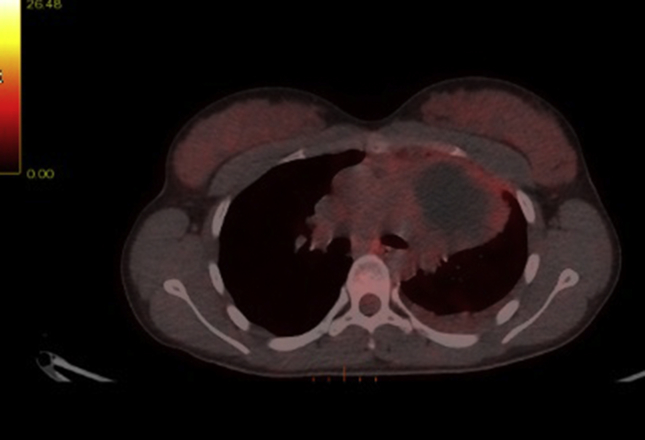

A 18F-fluorodeoxyglucose positron emission tomography (FDG-PET) scanning showed increased FDG uptake in the lateral/caudal area of the cyst with more focal changes in the basal. There was pleural effusion with slightly increased FDG uptake, as well as moderate FDG uptake in an enlarged lymph node in the mediastinum station 6 and slightly FDG uptake in the small lymph node station 1L (Fig. 3).

Fig. 3.

A PET/CT scanning showing a cystic process in the anterior mediastinum left side, with increased FDG uptake.